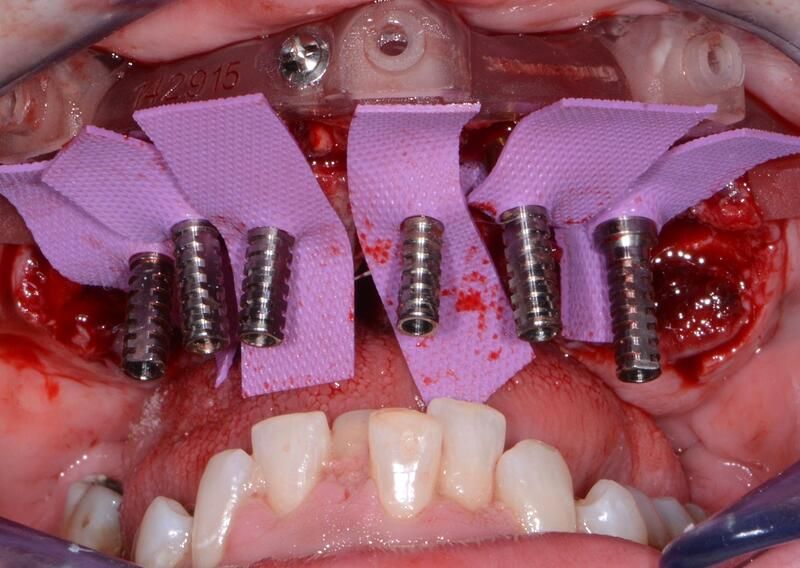

術(shù)中過(guò)程

完成植入后全景照片